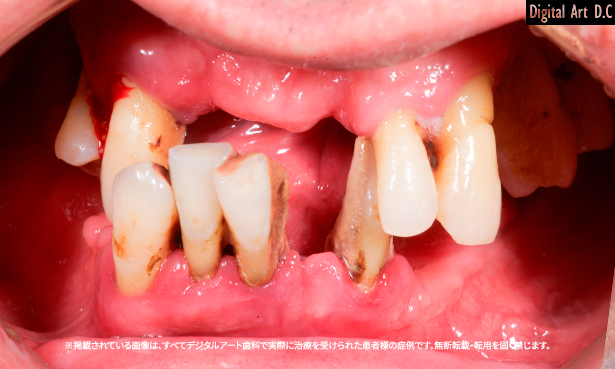

4. 시술 대상

다음과 같은 경우 부산전체임플란트를 고려할 수 있습니다.

- 상악 또는 하악의 치아가 모두 상실된 경우

- 틀니로 인한 통증 또는 불편을 겪는 경우

- 잇몸뼈(치조골)가 일정 수준 이상 유지되어 있는 경우

- 전신 질환이 없어 수술이 가능한 경우